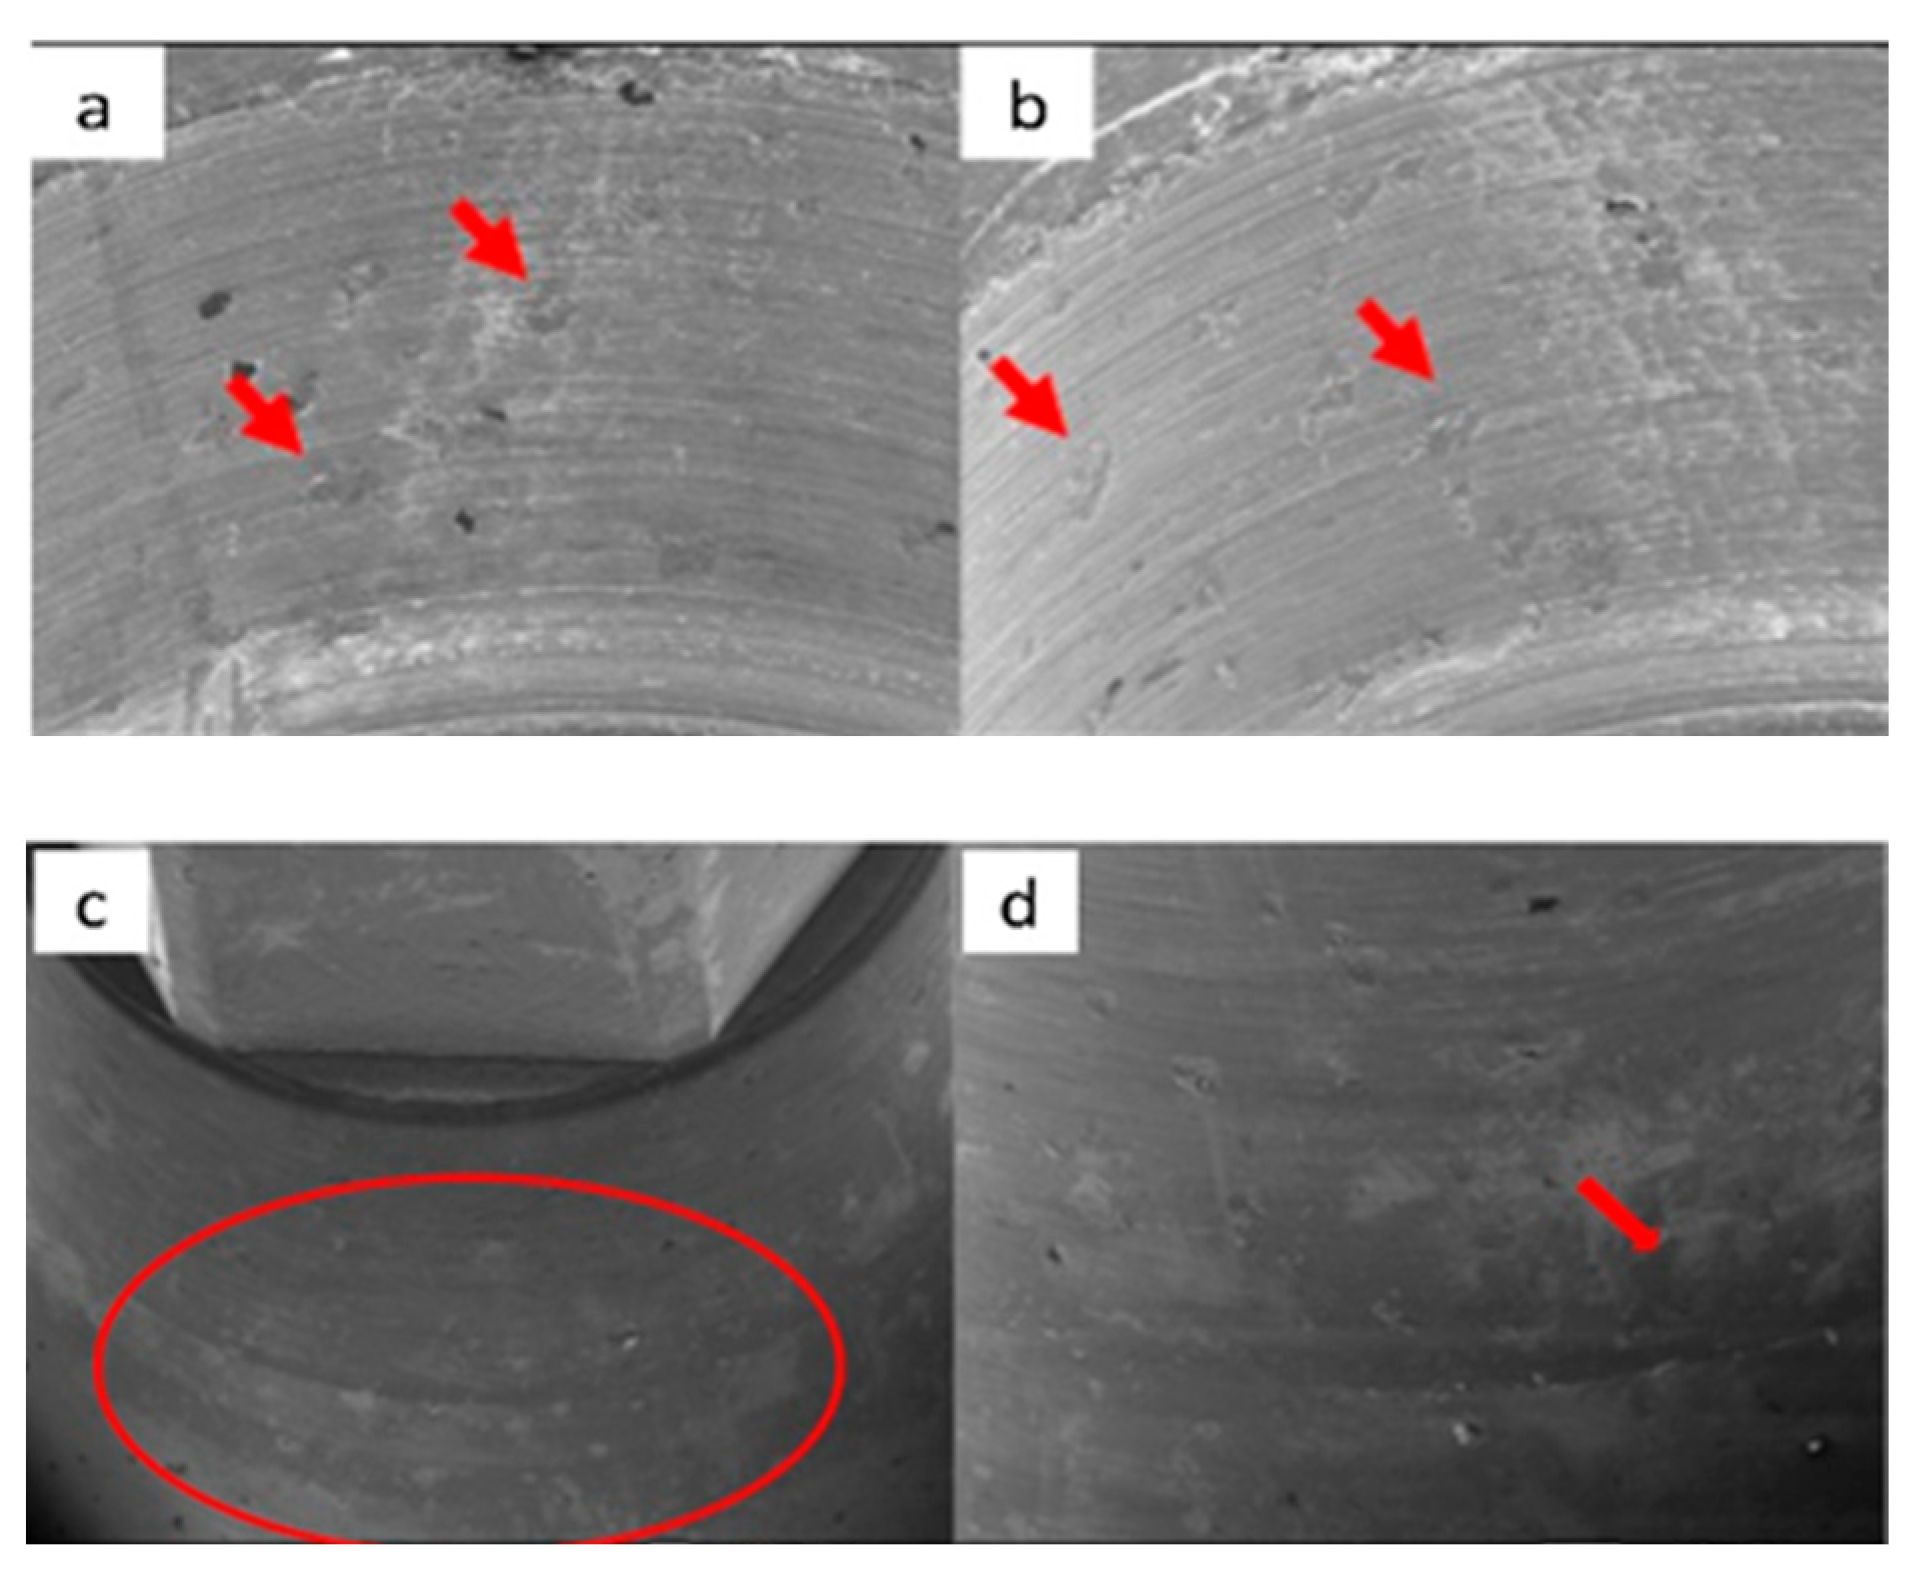

3.1. SEM

3.1.1. KL Implants

3.1.2. Essential Implants

3.1.3. SK2 Implants

3.1.4. Vega Implants

4.1. SEM Evaluation